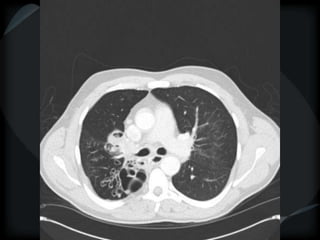

Septal Pattern – lymphatic/venous

 Secondary lobule outlined- interlobular septum

● Smooth – pulmonary veno-occlusive disease, mitral

stenosis, capillary hemangiomatosis, LC

● Beaded – lymphangitic carcinomatosis, lymphoma,

lymphangiomatosis, sarcoid

Rare = non-Langerhans’ cell histiocytosis (bone+pleura)

amyloidosis

smooth

LC

beaded

PHTN – PA 39mm

39.2mm

PHTN and septal thickening

? PVOD